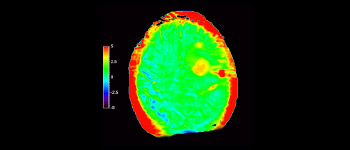

Neurologische Leiden stellen eine schwere Belastung dar. Philips hat es sich zum Ziel gesetzt, hochwertigste Neuro-Bildgebung zu ermöglichen – für eindeutige Diagnosen und eine schnelle Therapie. Wenngleich die MRT heutzutage den Goldstandard in der neuroradiologischen onkologischen Bildgebung darstellt, kann die Genauigkeit beim Tumor-Grading und den Nachsorgeuntersuchungen noch weiter verbessert werden. 3D APT (Amide Proton Transfer) ist eine einzigartige, kontrastmittelfreie Methode zur MR-Tomographie des Gehirns, die den Bedarf nach einer sichereren Diagnose in der Neuroonkologie erfüllt. 3D APT nutzt das Vorhandensein von endogenen zellulären Proteinen zur Erzeugung eines MR-Signals, das direkt mit der Zellproliferation, einem Marker für Tumoraktivität, korreliert. 3D APT kann geschulte medizinische Fachkräfte dabei unterstützen, gering differenzierte von hochdifferenzierten Gliomen und Tumorverhalten von Behandlungseffekt zu unterscheiden1.

mit 3D APT